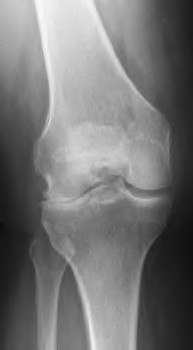

A 67 year-old woman sustained an ACL tear while playing basketball when she was 35 years-old. She has noted progressive leg deformity and episodes of giving way, and now has pain preventing activity. Non-operative management has failed to provide relief. Treatment should consist of?

The radiograph seen in Figure A reveals varus alignment of the knee, with medial tibial deficiency; from this X-ray the patient appears to have unicompartmental arthritis. Treatment options for unicompartmental arthritis include high tibial osteotomy, interpositional arthroplasty, unicondylar knee replacement and total knee replacement. Interpositional arthroplasty became popular in the 1950’s when early outcomes analysis seemed to indicate good results; long term follow up in one study found 0/12 excellent results, with all patients requiring conversion to TKA. This procedure is no longer recommended due to the poor long term outcomes.

While an osteotomy is still used for young and active patients, unicompartmental or total knee arthroplasty have largely replaced this treatment in older patients. Advantages of UKA and TKA include more predictable relief of pain, quicker recovery, and better long-term results. Criteria for UKA include limited unicompartmental disease, no more than a fixed 10 degrees of varus or 5 degrees of valgus deformity from neutral and an intact anterior cruciate ligament with no signs of medial lateral subluxation of the femur on the tibia; this patient is therefore not a good candidate for this procedure.

Total knee arthroplasty can be used to provide predictable pain relief in a patient with unicompartmental and tricompartmental degenerative disease and varus malformation of the knee and for this patient is the best option.